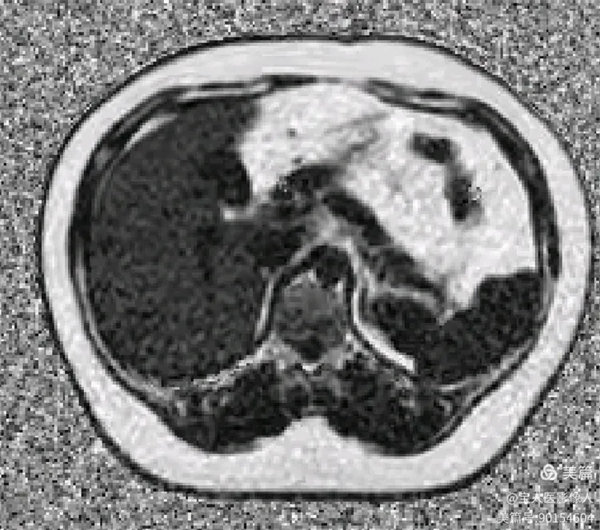

圖5

FatFrac圖(脂肪分量圖)肝實質(zhì)信號均勻性升高。

圖6

PDFF測值,測量全肝實質(zhì)多部位的脂肪分?jǐn)?shù)值12%—17%,提示:脂肪肝,MR-PDFF,二級,中度。